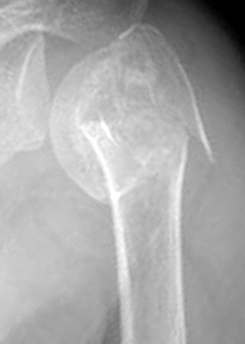

상완골은 어깨에서 팔꿈치까지 이어진 긴 뼈로위쪽부터 1/3씩 나누어 근위, 중간, 원위부로 나눌 수 있습니다. 그 중 근위부 골절은 어깨 관절부에서 발생하는데 뼈가 약한 노인들이 넘어지면서 잘 생깁니다.

골절부의 어긋남과 부러진 골편의 수 따라 비전이성 골절, 이분, 삼분 및 사분골절로 나눕니다. 비전이성 골절이 가장 흔합니다.

위 상완골의 골절로 3개 부분이

위 상완골의 골절로 3개 부분이 어긋나 있는 3분 골절

넘어진 후에 어깨에 통증과 붓기가 심하고 피멍이 관찰되면 의심해야 합니다. 엑스레이 사진으로 쉽게 진단이 되며 골절 양상의 세밀한 진단이나 수술 전 검사로 CT를 찍는 경우가 있습니다.